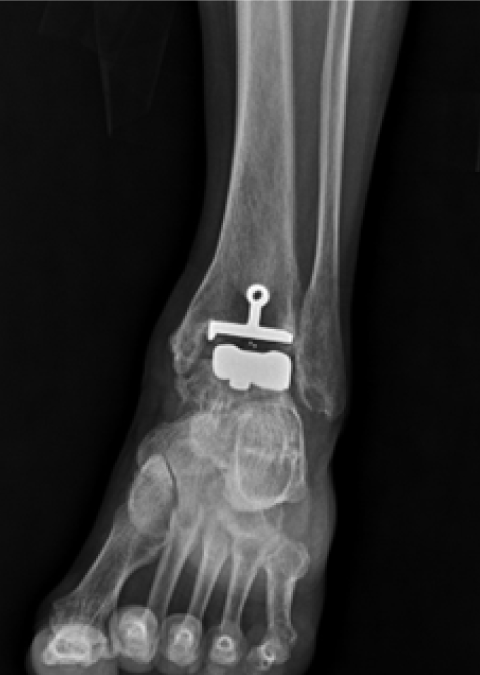

발목관절염 수술 전

2020.06.26

발목관절염 수술 후

2022.10.14

ㆍ환자 동의를 받은 자료이며, 이미지 사진은 실물과 다를 수 있습니다.

ㆍ모든 자료는 새움병원 자료입니다.